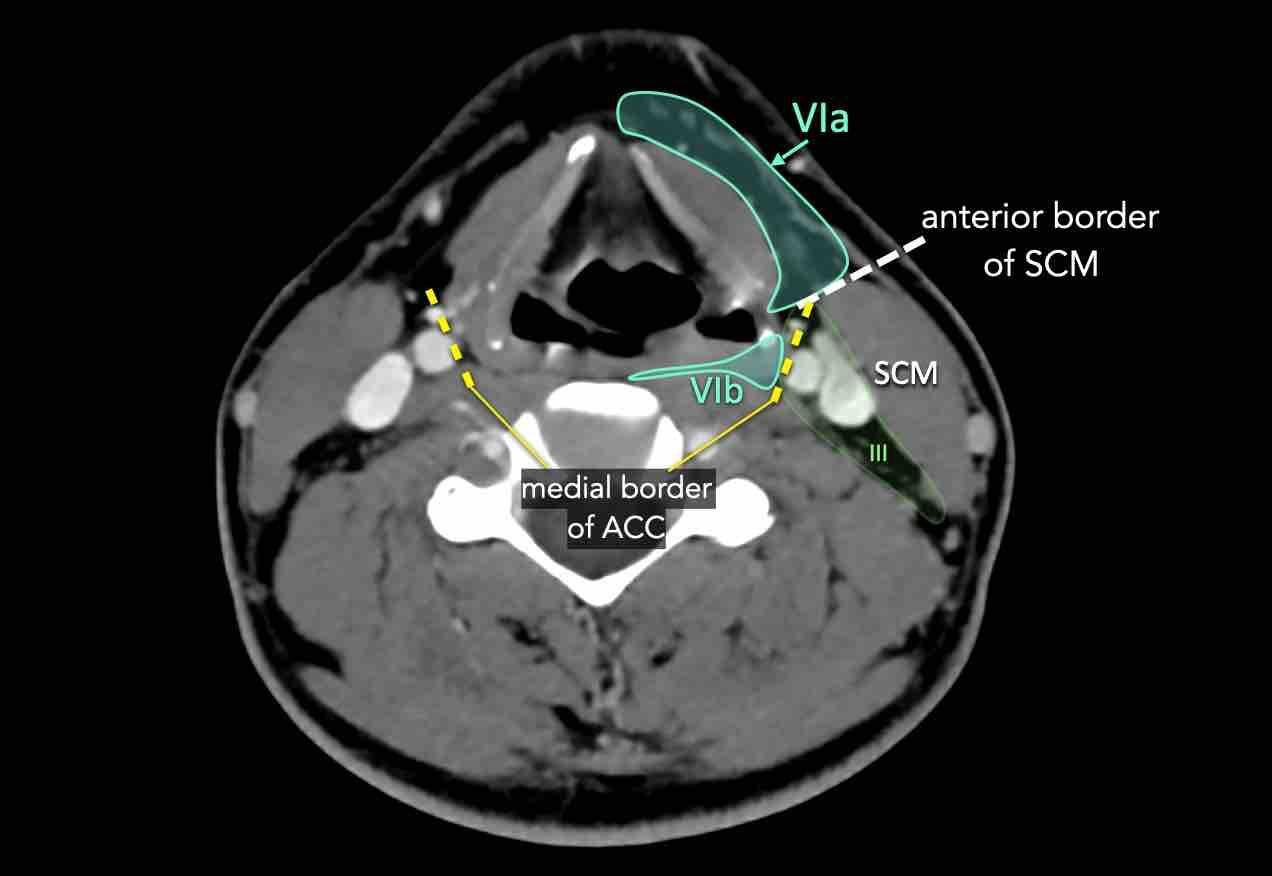

VI – Cổ trước

Tầng này chứa các hạch tĩnh mạch cảnh trước nông (tầng VIa) và các hạch sâu hơn bao gồm hạch trước thanh quản, trước khí quản, cạnh khí quản và hạch thần kinh thanh quản quặt ngược (tầng VIb).